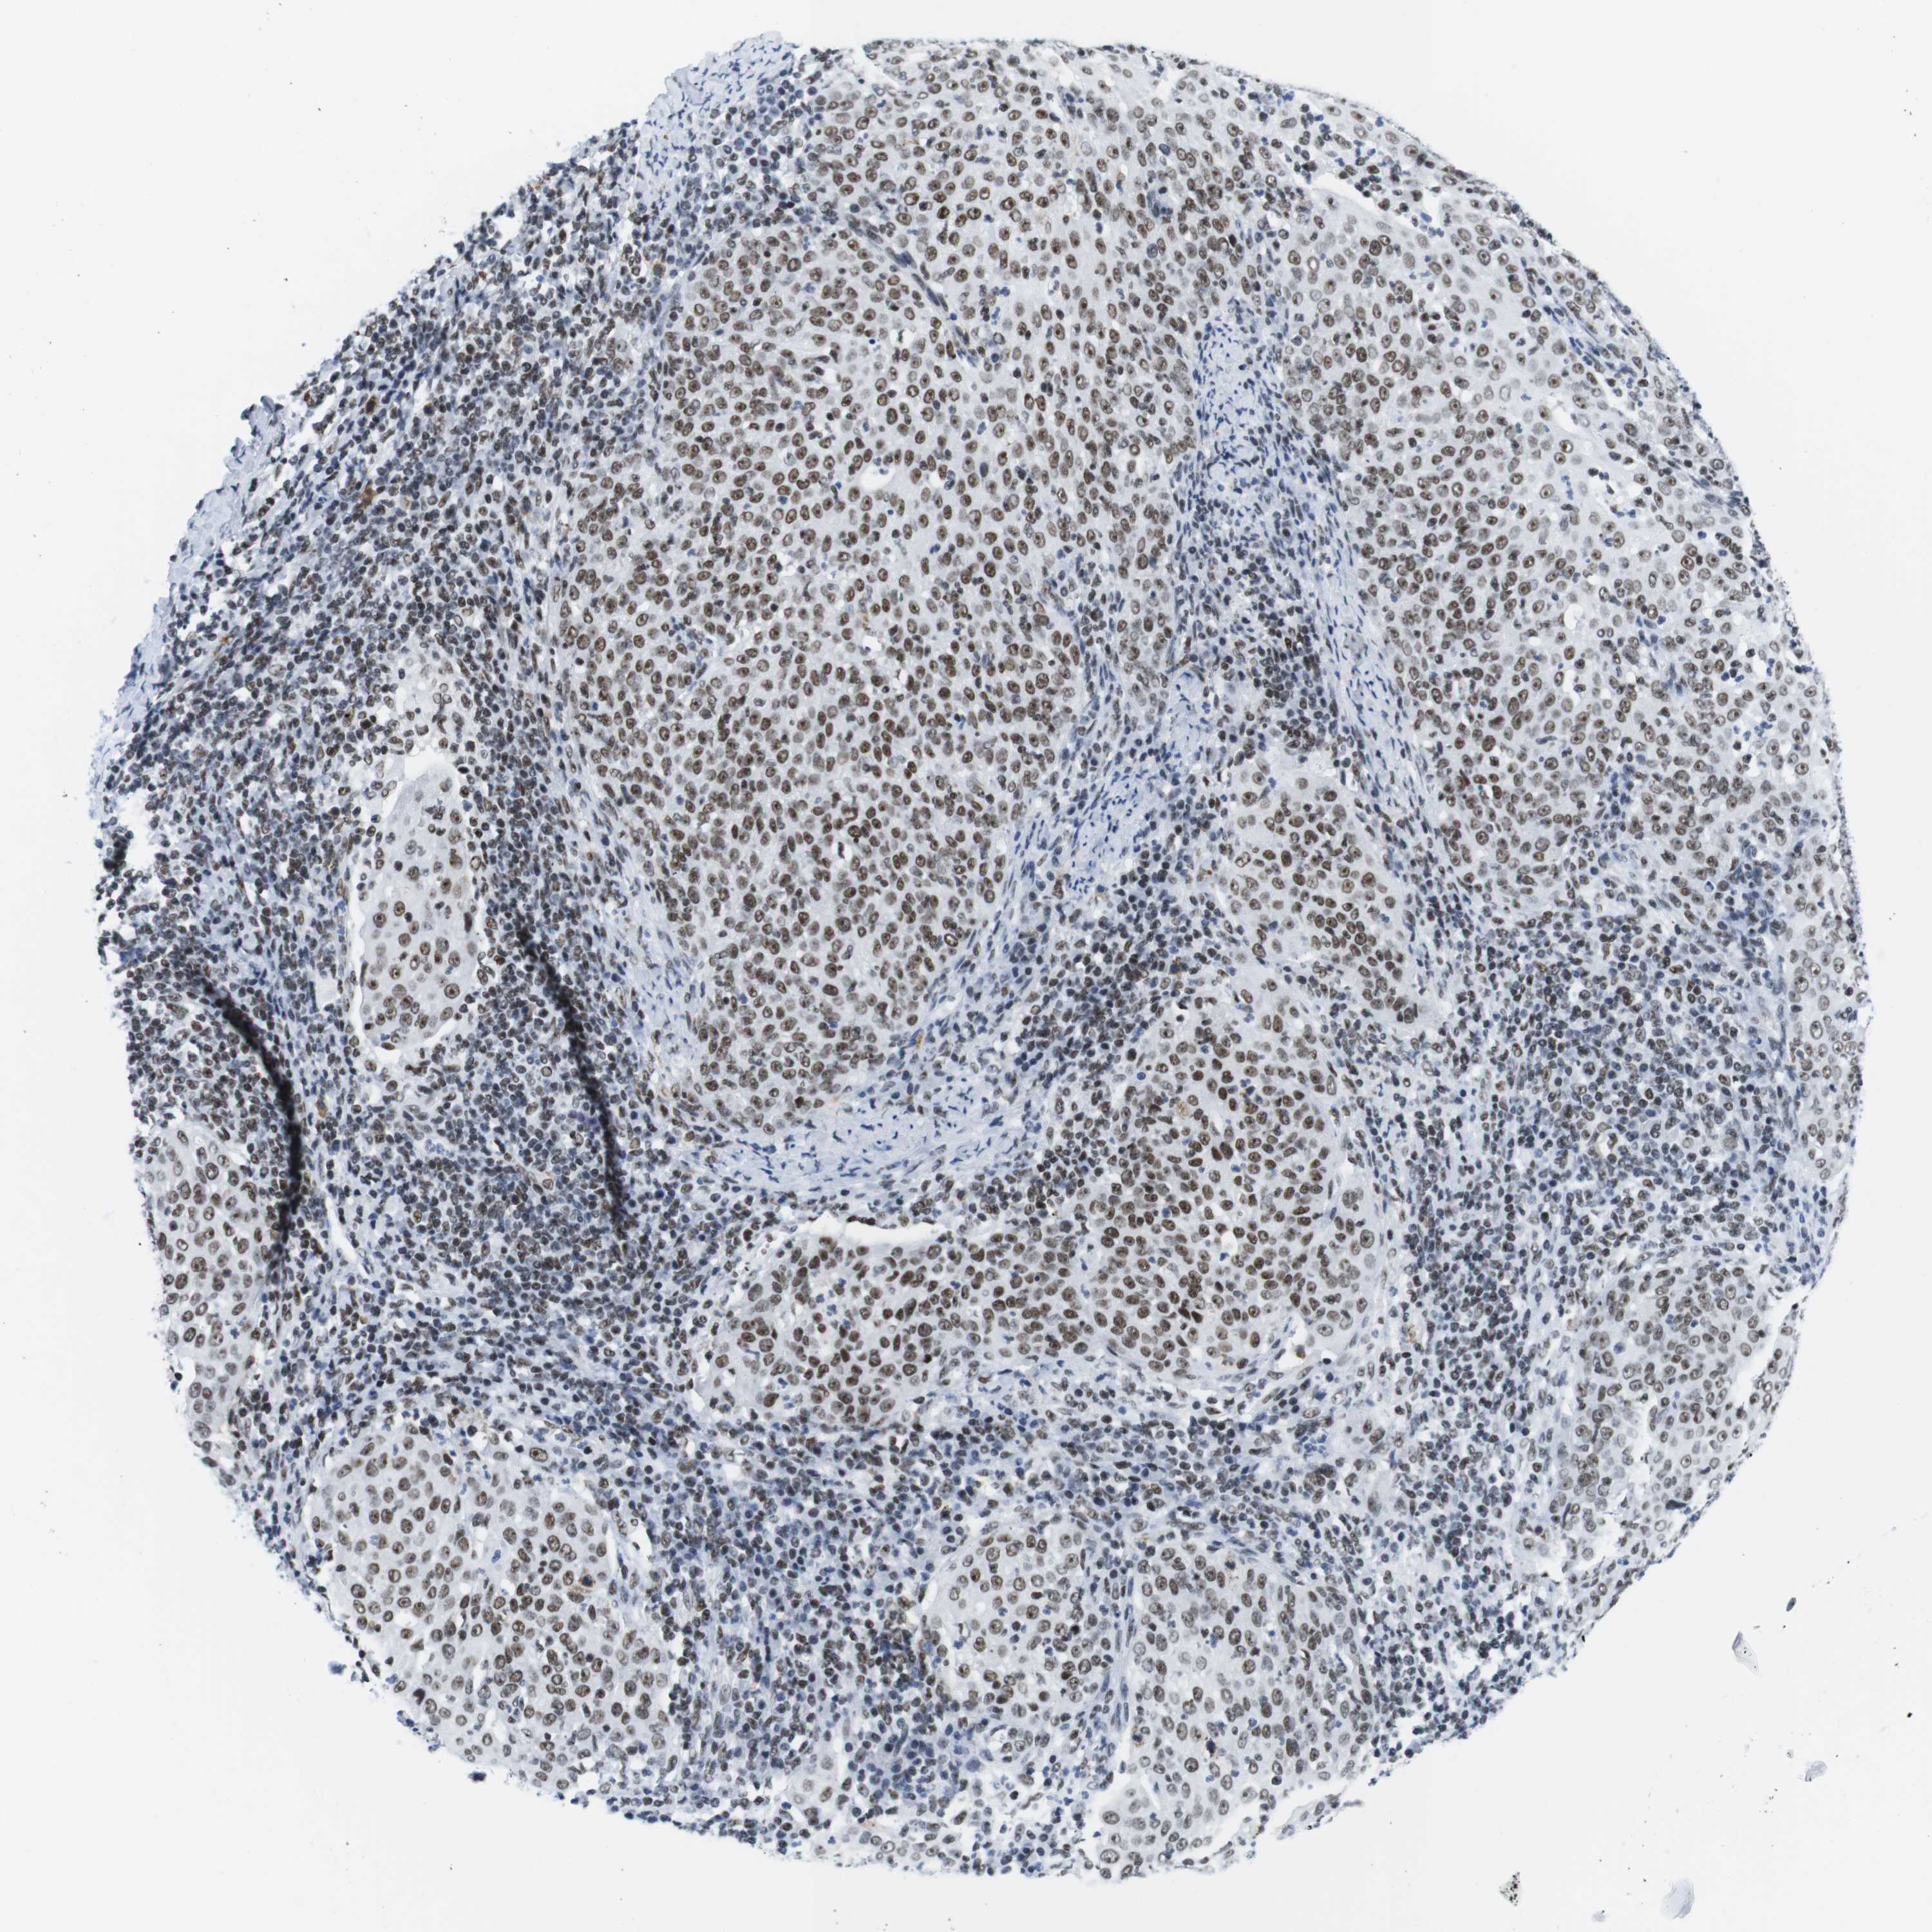

CERVICAL CANCER - Protein expressioni

A mouse-over function shows sample information and annotation data. Click on an image to view it in a full screen mode. Samples can be filtered based on level of antibody staining by selecting one or several of the following categories: high, medium, low and not detected. The assay and annotation is described here.

Note that samples used for immunohistochemistry by the Human Protein Atlas do not correspond to samples in the TCGA dataset.

Antibody stainingi

Antibody staining in the annotated cell types in the current human tissue is reported as not detected, low, medium, or high, based on conventional immunohistochemistry profiling in selected tissues. This score is based on the combination of the staining intensity and fraction of stained cells.

Each image is clickable and will lead to virtual microscopy that enables deeper exploration of all samples and also displays staining intensity scores, fraction scores and subcellular localization as well as patient and tissue information for each sample.

Antibody HPA002134

Antibody CAB016293

Staining

High

Medium

Low

Not detected

Intensity

Strong

Moderate

Weak

Negative

Quantity

>75%

75%-25%

<25%

None

Location

Nuclear

Cytoplasmic/membranous

Cytoplasmic/membranous,nuclear

Squamous cell carcinoma, NOS

Adenocarcinoma, NOS